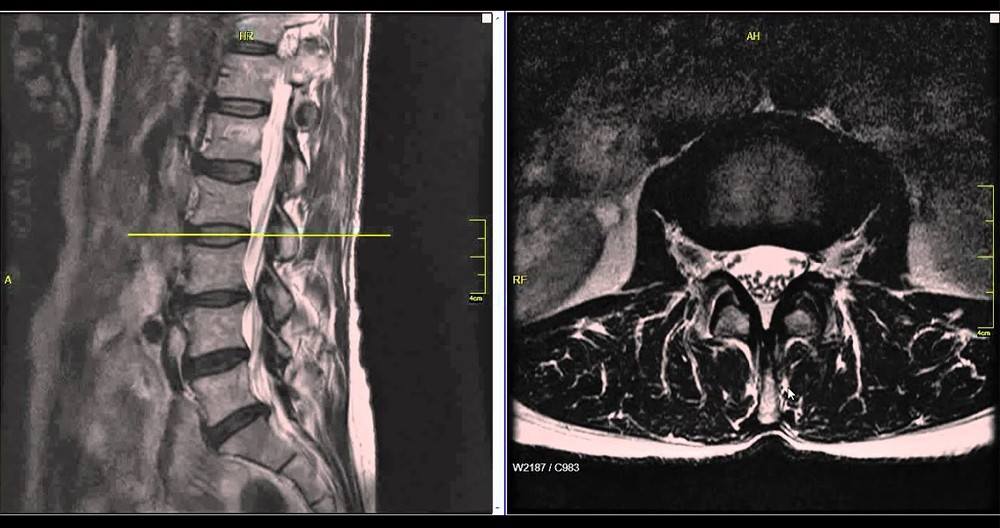

人類自從進(jìn)化到站立行走以后,我們的腰椎成為了支撐軀干的中心。無論是站立還是坐位,腰部承受了60%以上的體重。腰椎老化退變成為了現(xiàn)代人面臨的一大問題。根據(jù)衛(wèi)生部的統(tǒng)計(jì)數(shù)據(jù),我國(guó)腰椎疾病患者人數(shù)已經(jīng)超過了2億,成年人腰椎病發(fā)病率分別為80%,男女比例為3:1,20-40歲的患者占到了64%以上的比例。其中腰椎間盤突出癥(腰突癥)患者人數(shù)占全國(guó)總?cè)藬?shù)的15.2%,每100人就有15人患病。發(fā)病率僅次于感冒。

對(duì)于腰椎間盤突出癥患者來說,非手術(shù)的治療方法是首選。80%的人可以通過理療、牽引、靜臥休養(yǎng)和藥物治療來自我緩解。一般,經(jīng)過3個(gè)月的保守治療以后,如果狀況不見好轉(zhuǎn)或反而加重了,很有可能醫(yī)生會(huì)建議手術(shù)。

外科手術(shù),作為椎間盤突出癥的最后治療手段并不總是解決問題的最佳方法。其實(shí),任何椎間盤突出切除術(shù)都會(huì)對(duì)椎間盤和鄰近的部分組織造成難以避免的創(chuàng)傷。特別是病狀還沒有發(fā)展到一定要做手術(shù)的狀況。在這種情況下手術(shù)的破壞程度往往要超過病狀帶來的危害。椎間孔鏡微創(chuàng)手術(shù)也不列外,要摘除椎間盤突出來的部分,纖維環(huán)內(nèi)肯定會(huì)留下一個(gè)相當(dāng)大的窟窿,而連纖維環(huán)內(nèi)最微小的裂隙都有可能引起椎間免疫反應(yīng)和炎癥,所謂的盤滲漏綜合征。不過,保守治療無效而癥狀已經(jīng)無法忍受的情況下,還有什么選擇呢?有沒有更合理的治療方法來解除腰病人士的痛苦?美國(guó)脊柱外科醫(yī)生Dr. Kevin Pauza也同樣思考過這些問題,最終研發(fā)了Discseel?Procedure?DST椎間盤修復(fù)再生術(shù)。

DST療法是由美國(guó)脊椎外科醫(yī)生及其團(tuán)隊(duì)研發(fā)的,自2010年開始應(yīng)用于臨床手術(shù)治療。截止到2023年6月,已經(jīng)治療了8000余病例。目前,在亞洲地區(qū),只有日本的野中腰椎醫(yī)院擁有官方授權(quán)。Discseel? Procedure?DST椎間盤修復(fù)再生治療與外科手術(shù)不同,不進(jìn)行開刀,只需通過0.8mm的穿刺針插入椎間盤,注射生理制劑。注入的生理制劑不僅能夠修補(bǔ)受損的纖維環(huán),阻止髓核流出,還能促進(jìn)盤內(nèi)組織再生,使椎間盤恢復(fù)一定的彈性,從根本上治療椎間盤,達(dá)到緩解癥狀的目的。Discseel?Procedure?DST椎間盤修復(fù)再生術(shù)可當(dāng)天出院,而且適用于其他手術(shù)失敗或復(fù)發(fā)的患者,甚至適合80多歲高齡的患者。此外,DST椎間盤修復(fù)再生療法的復(fù)發(fā)率低,有效率高達(dá)70%以上。